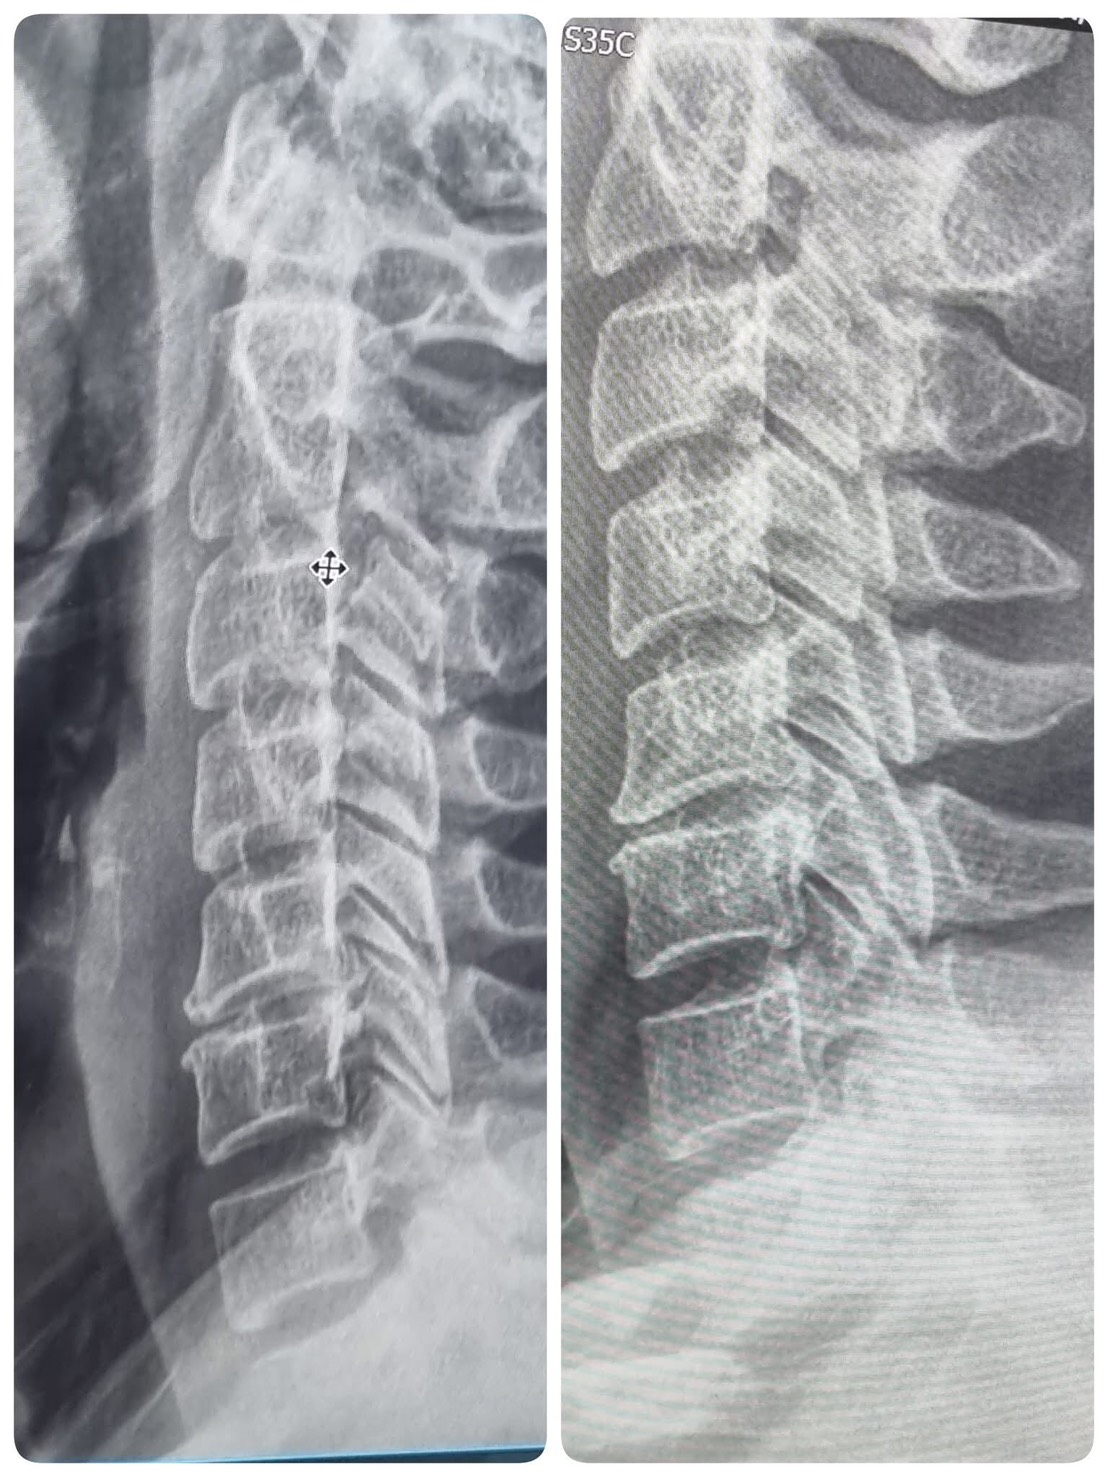

กระดูกสันหลังคด (Scoliosis) สังเกตอย่างไร และรักษาได้ไหม?

กระดูกสันหลังคดเป็นภาวะที่พบได้บ่อยตั้งแต่วัยรุ่น หากตรวจพบเร็ว สามารถรักษาและปรับสรีระให้ดีขึ้นได้ด้วยกายภาพบำบัด